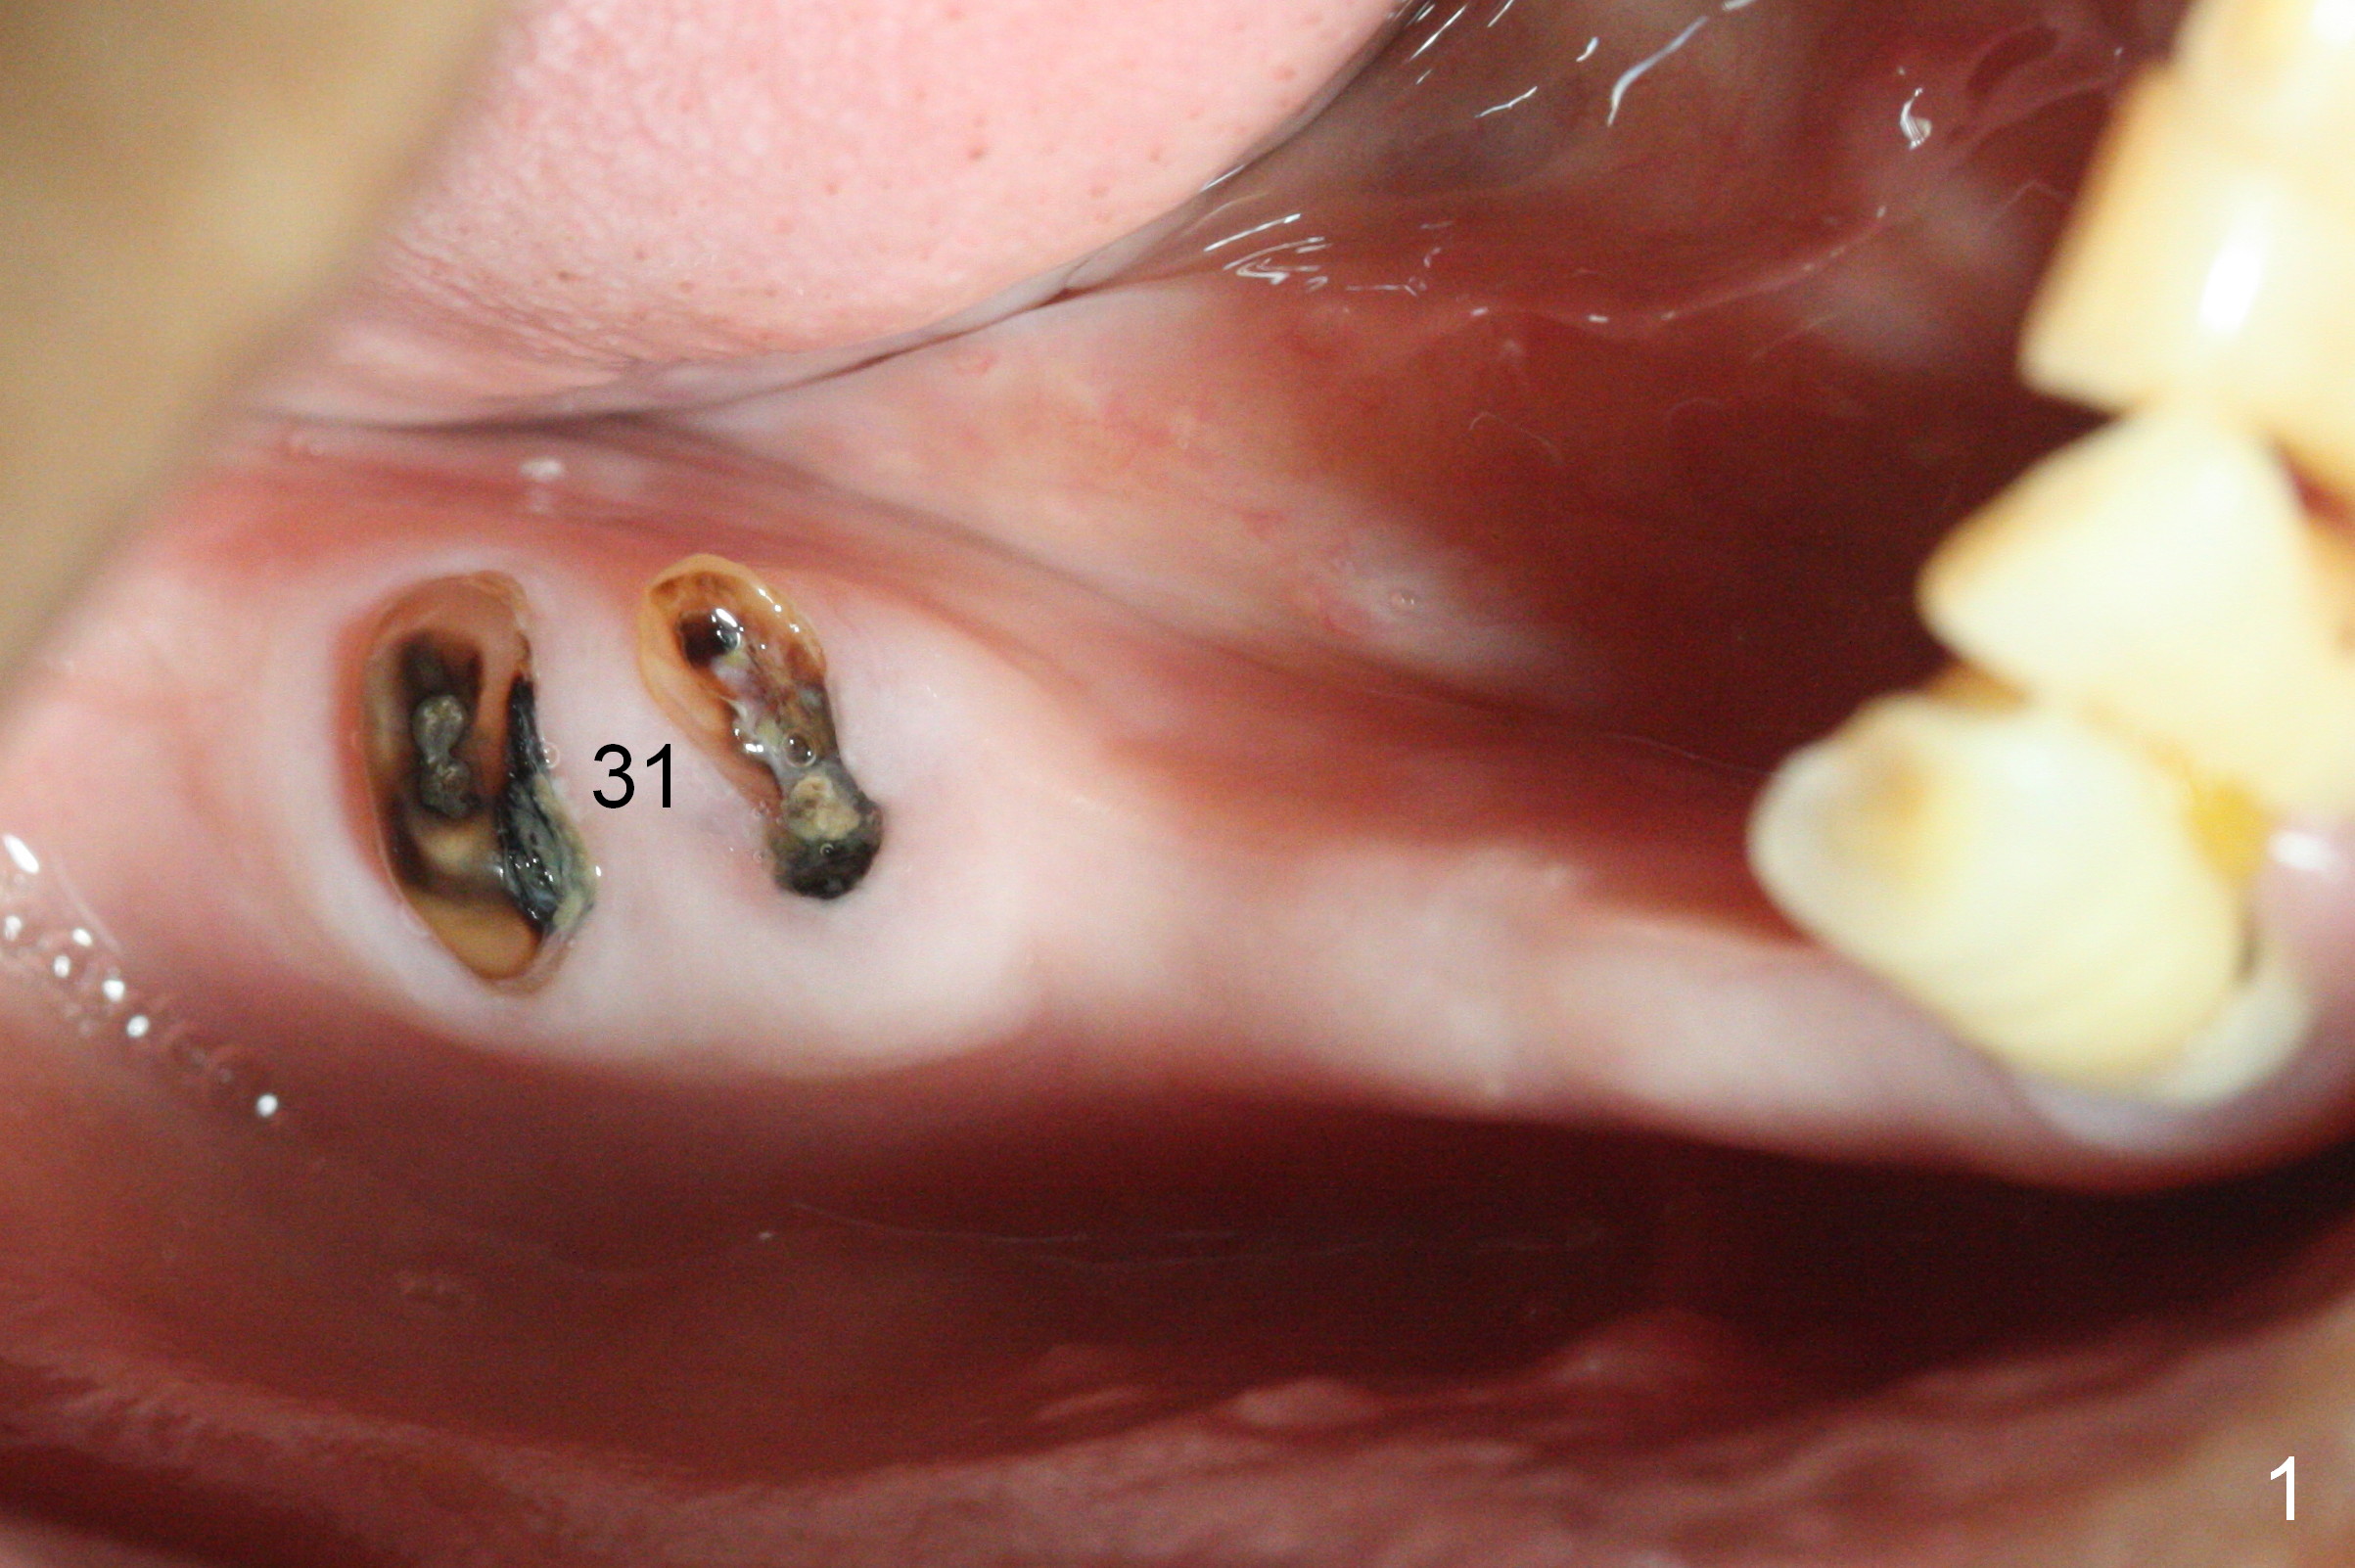

A 72-year-old man will return for #31 immediate implant several months after that at #21 (Fig.1,2). After extraction (no Antibiotic), separation of the gingiva (Fig.1) from the septum (Fig.3 S (white curved line: the upper border of the septum)) and use of starter drill, place the 13 mm stopper (Fig.4 red) in the 2 mm initial drill (green) against the septal top as a reliable landmark for osteotomy.